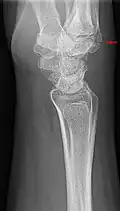

Carpal boss in der seitlichen Röntgenaufnahme der Handwurzel. -